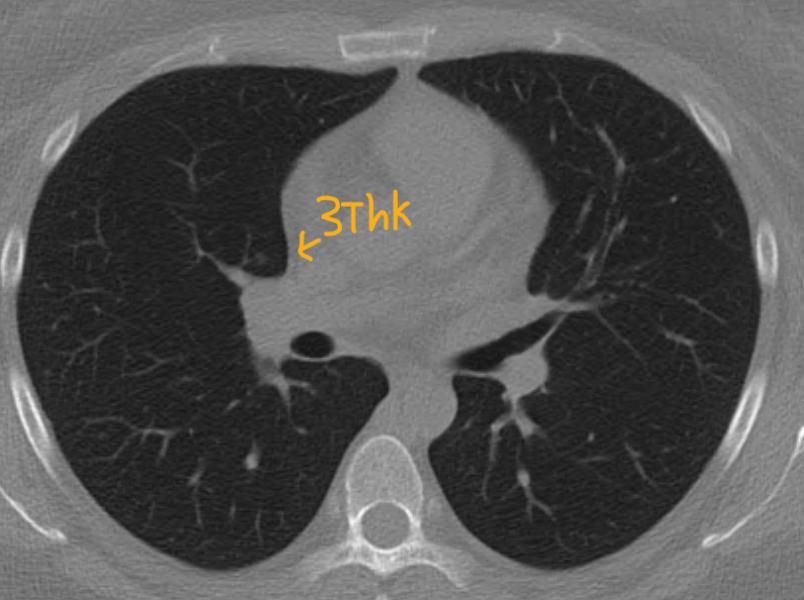

3thk 적혀있는거 제외하고 1thk입니다

CT를 확인하시고 간유리음영이라고 들었는데 영상을 직접 확인하시고나니 조금씩 차이가 나서 헷갈리시는 것 같습니다.

일단은 첫번째 영상은 크기가 애매해서 말씀드리기는 어려운 것 같구요